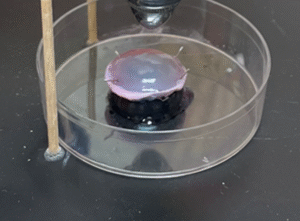

Treatment of the inoculated cornea with UV-C for 15 seconds at a distance of 10 mm.